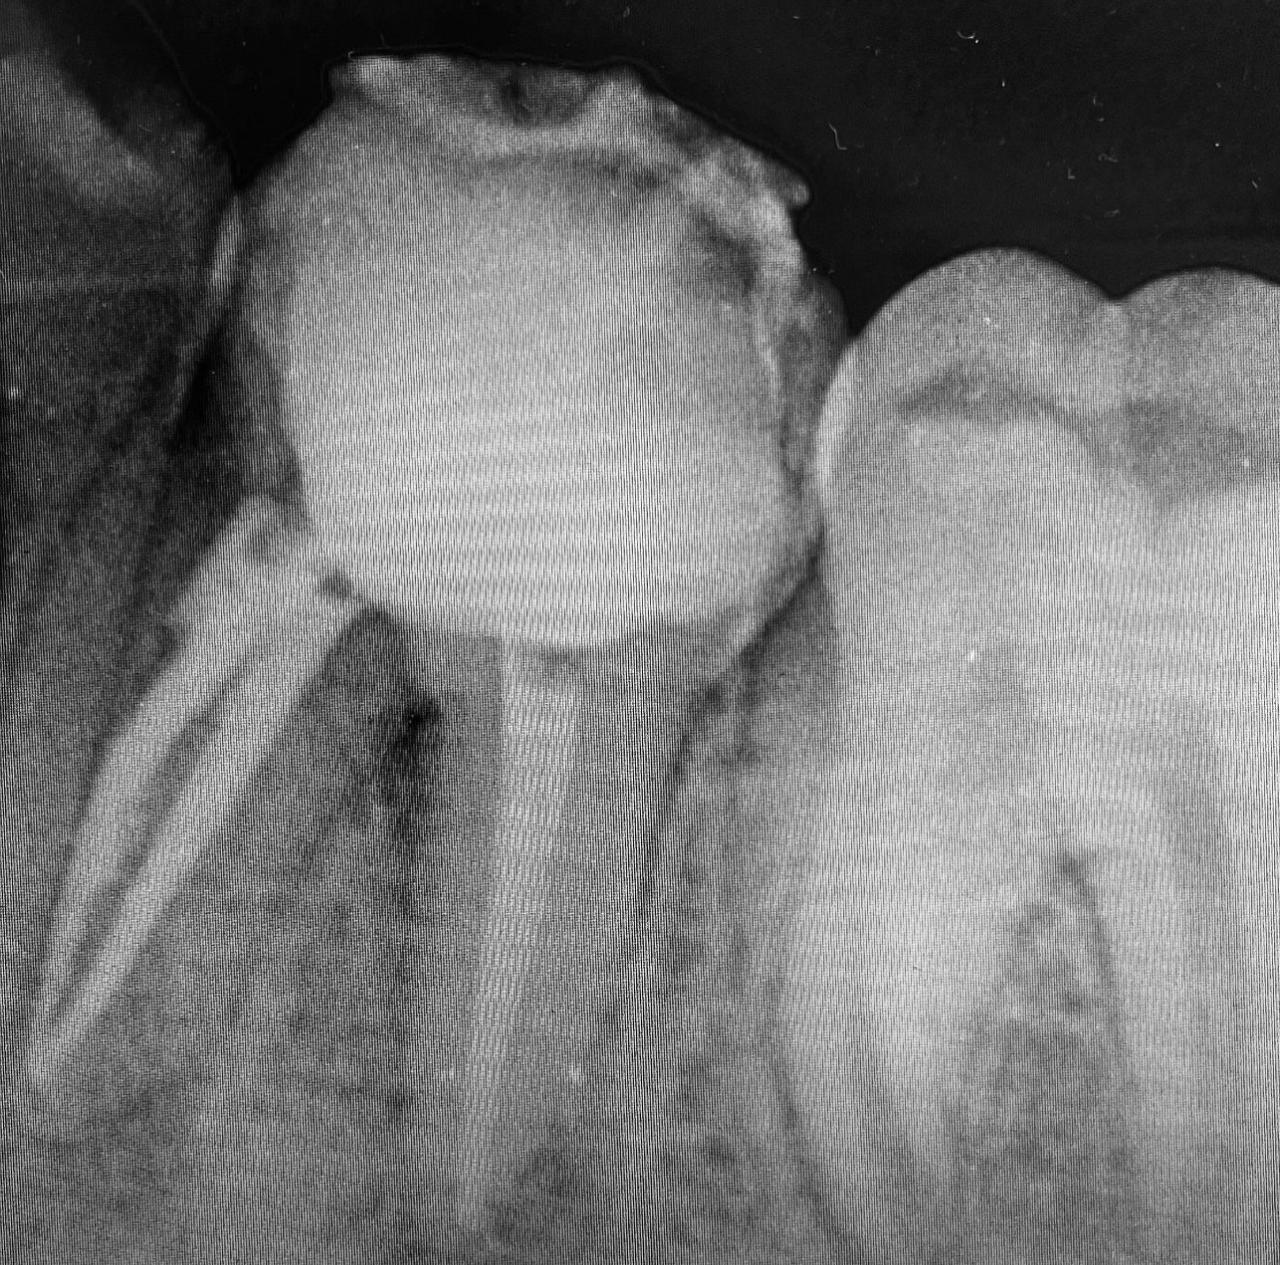

Radiographic Analysis

Radiographs revealed:

These findings confirmed the failure of the initial root canal, most likely due to incomplete disinfection or persistent bacterial infection.